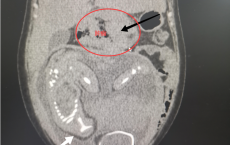

孩子反复鼻塞、流鼻血和臭鼻涕,不一定是鼻炎!专家提醒:儿童鼻腔异物不容小觑!

桂林市妇幼保健院接诊一名2岁多女童,因鼻腔内藏荔枝核壳两个多月,导致反复鼻出血、流臭涕。经鼻内镜在麻醉下成功取出已引发肉芽增生的异物。医生提醒,儿童鼻腔异物常见于2-5岁幼儿,可能由坚果、小玩具等引起,严重时可致感染、穿孔甚至窒息。出现单侧流脓、臭味、鼻出血等症状应尽早就医,切勿自行处理。加强看护与安全教育是预防关键。